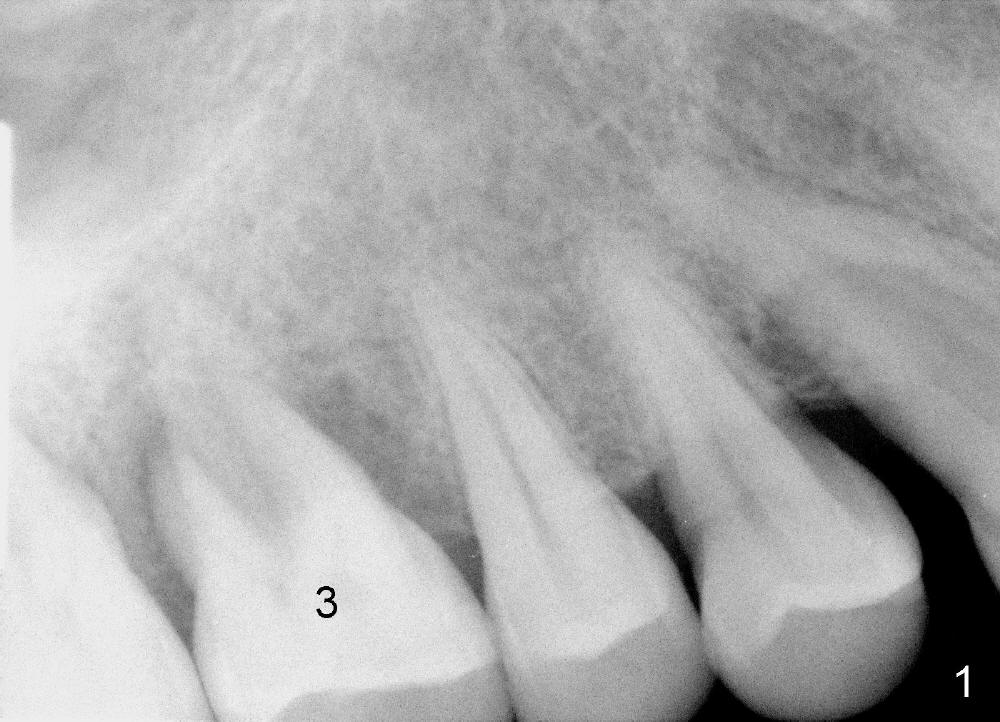

The tooth #3 has severe periodontitis with probably endodontic lesion (Fig.1,2). The patient is a 43-year-old man with apprehension of dentistry. An acute infection causes pain and tooth shift (Fig.4,5). A 7x17 mm immediate implant is planned (Fig.3). The palatal socket is shallow (Fig.6 P), corresponding to severe recessive palatal root (Fig.5 P). The osteotomy is created mainly in the buccal socket (Fig.6 B), exactly in the lingual slope of the septum. Initially osteotomes are used, followed by tap placement (Fig.7 T (4.5x20 mm at the depth of 17 mm). When the implant is placed as planned (Fig.8 I), there is more vertical contact (Fig.8 red line) than that associated with the tap (Fig.7 red line). The corresponding insertion torque is between 50 and 60 Ncm. There is only one small gap buccally, which is filled with bone graft (Fig.9 <). After the insertion of a short abutments with vertical slots (Fig.9,10 A), perio dressing is used to cover the wound. The palatal socket is expected to heal uneventfully (Fig.10 P). In fact, it does in 7 days (Fig.12 P); the bone graft in the mesiobuccal aspect is healing and stabilized (Fig.11 <). By two weeks postop, the mesiobuccal socket has healed (Fig.13 <). With removal of a diseased tooth, our body has amazing power to heal.